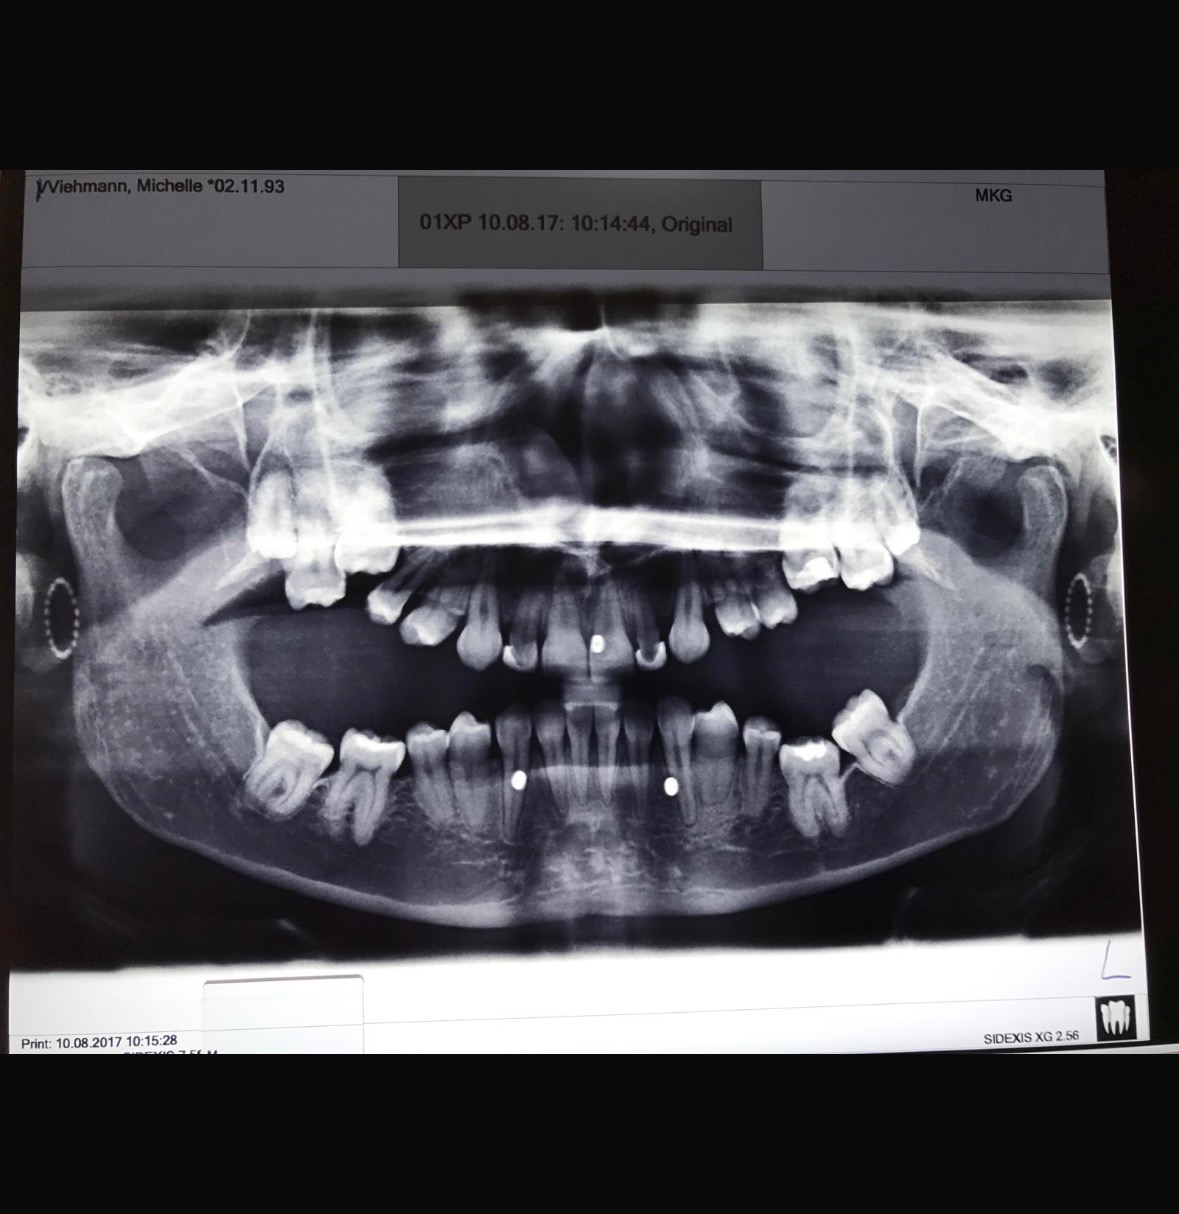

2019 große Operation komplette Kieferumstellung (Bruch des gesamten Kiefers und neu Verschraubung) mit der Annahme danach wird alles gut und ich kann endlich vernünftig kauen. Nachdem Schmerzhafte Tage und schwierige Monate der flüssigen Ernährung überstanden waren und die nächsten Termine zur Weiterbehandlung anstanden wurde klar dass das Ergebnis nicht 100%ig erreicht wurde und Fragen aufkamen wie es nun weitergeht. Anschließend bekam ich Plastikschienen über meine Zähne damit mein Kiefer sich nicht wieder zurückbildet und ich meine Muskulatur trainiere. Zum ersten Mal hinten kauen, endlich.

leider gehen die Schienen ständig zu Bruch und halten härtere Lebensmittel wie knusprigen Pommes oder Brötchen nicht stand.

Die Schienen trage ich jetzt seit über 5 Jahren, spätestens alle 6 Monate brechen sie kaputt.

Jetzt habe ich einen tollen Zahnarzt mit viel Verständnis und Ahnung gefunden der mich weiterbehandeln möchte und mir eine gute Behandlungsmethode vorgeschlagen hat.

Ich bekomme eine Teleskop Prothese, langanhaltenen und funktionierende Lösung um endlich richtig kauen zu können und den Kiefer ohne Schmerzen zu halten.